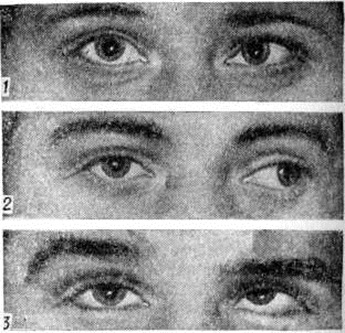

Содружественное косоглазие может быть врождённым и приобретённым; первичным (без видимой патологии глаза) и вторичным (развивающимся при снижении зрения одного глаза при катаракте, бельме роговицы, патологии сетчатки, зрительного нерва и других заболеваниях глазного яблока); постоянным и периодическим, неаккомодационным (не исчезающим после коррекции аметропии), частично аккомодационным (уменьшающимся под влиянием коррекции аметропии) и аккомодационным (устраняющимся коррекцией аметропии); монолатеральным (косит один определённый глаз); альтернирующим (попеременное отклонение глаз); сходящимся (конвергирующим) — зрительная ось одного из глаз отклонена к носу (рисунок 1, 1)\ расходящимся (дивергирующим) — зрительная ось отклонена к виску (рисунок 1, 2); суправергирующим — отклонение одной из осей кверху (рисунок 1,5); инфравергирующим — отклонение одной из осей книзу.

Диагноз. Обследование больного начинают с анамнеза (время возникновения Косоглазие, его возможные причины, проведённое лечение, его влияние на положение глаз и зрение). Определяют остроту зрения каждого глаза и обоих глаз вместе, без коррекции и с коррекцией, характер Косоглазие (монолатеральное или альтернирующее) посредством пробы с прикрыванием глаз, вид Косоглазие по направлению отклонения глаза (сходящееся, расходящееся, вертикальное) и величину отклонения. Для практических целей вполне достаточно измерение угла Косоглазие по методу Гиршберга, который осуществляется зеркальным офтальмоскопом. Величина Косоглазие оценивается в градусах по положению светового рефлекса на роговице. Если рефлекс от офтальмоскопа располагается по краю зрачка, то угол косоглазия равен 15°, если на середине радужной оболочки — 25—30°, на лимбе — 45°, за лимбом — 60° и более (рисунок 2). При помощи светового прибора исследуют состояние бинокулярного зрения. Для суждения о состоянии бинокулярного зрения у детей младшего возраста используют пробу с призмой.